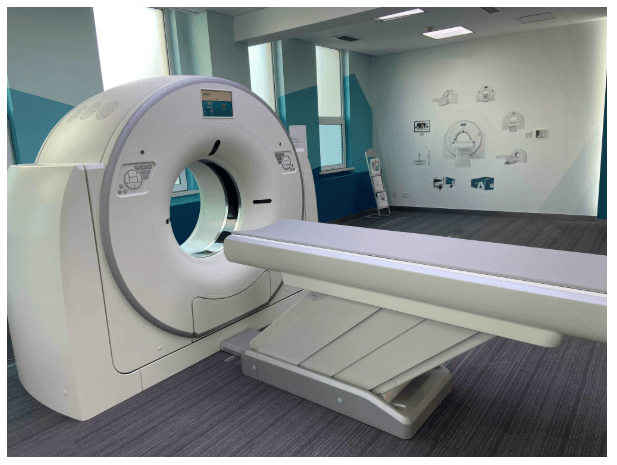

Spiral-CT

The product overview of x ray mri ct scanner 32 slice spiral ct scan machine for human

MSLCTX10 CT system is completely developed by Campo Imaging. It is the first CT product of Campo Image. P-Axial is a patent of MSLXTX10 CT system. It can obtain the thinnest CT images in the 0.275mm and has obvious advantages in the application of inner ear imaging and pulmonary nodule detection. 32-slice dual energy imaging extended the application of CT dual energy imaging. MSLXTX10 CT system provides high quality images and stable performance which can help hospitals to achieve comprehensive accurate diagnosis, and it will redefine the new standards of 32-slice CT imaging.